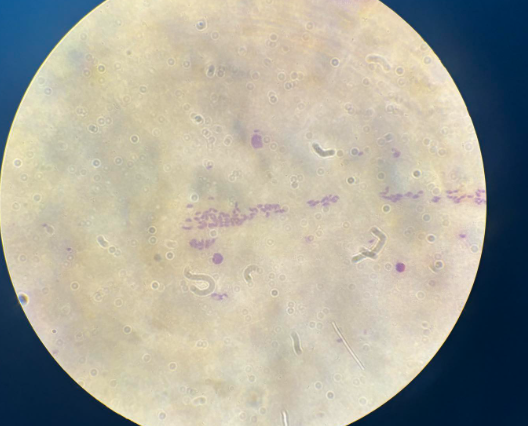

wuchnereria bancrofii mikrofilaria

loa loa mikrofilaria